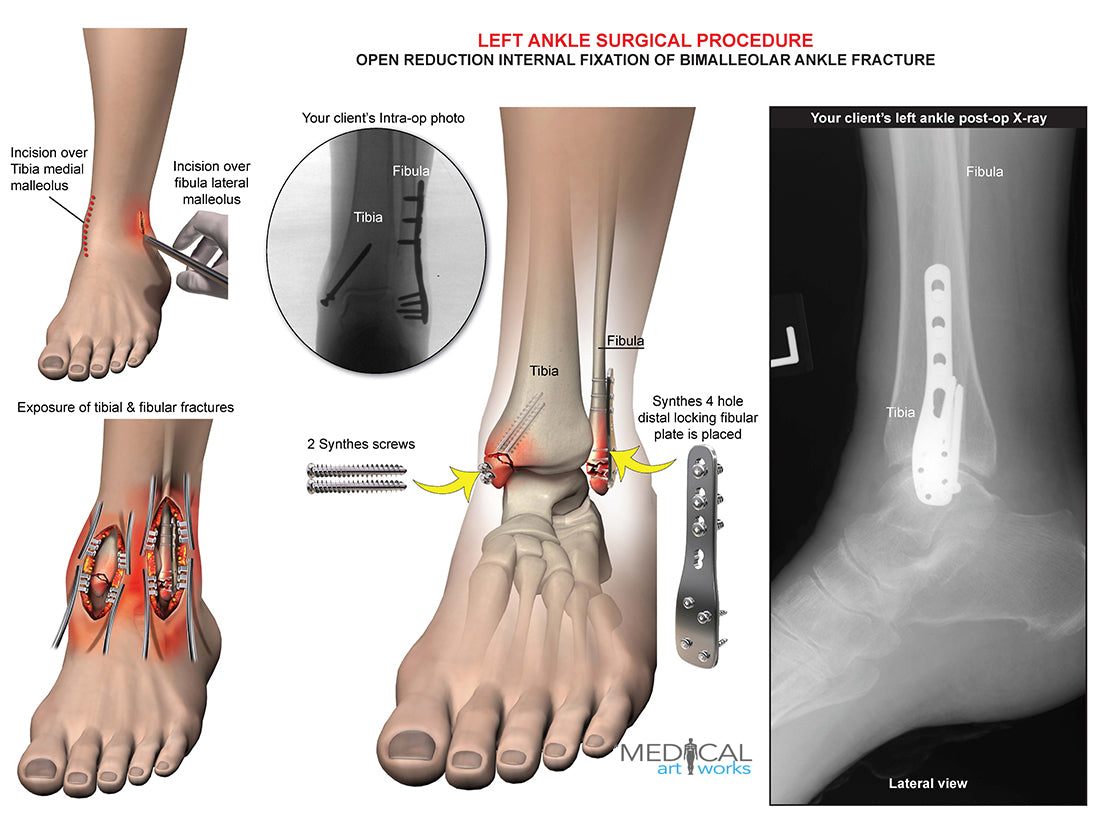

Left ankle and tibia bimalleolar fracture -ORIF

Left ankle and tibia bimalleolar fracture -ORIF

Open reduction internal fixation of bimalleolar ankle fracture. Synthes 4 hole distal locking fibular plate is placed, 2 Synthes screws. Add you own client's post-op x-ray.